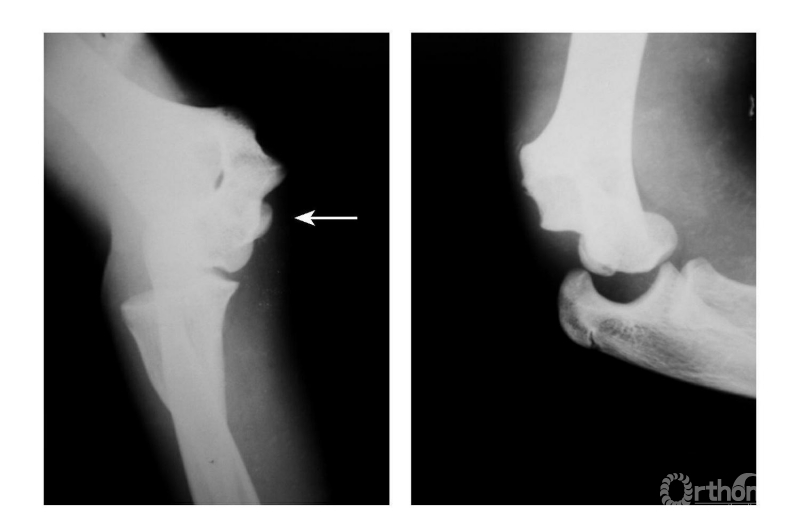

Ⅳ度损伤:

例2:肱骨内上髁Ⅳ度骨折并肘关节旋转性脱位(图10)。

图10